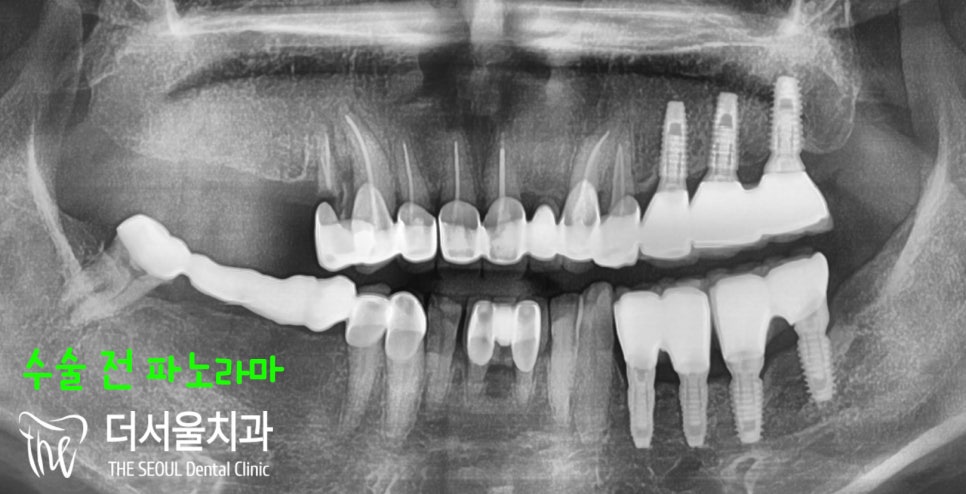

『초진 단계』

우선 문제를 호소하는 부위를

살펴보았습니다.

15, 16, 17번 치아 어금니가

모두 사라져 있는 상태네요.

골소실이 그렇게 심하게

일어난 것 같지 않아

뼈이식을 하지 않아도

될 것 같다는 예감이 들었습니다.

정확한 것은 파노라마 엑스레이로

확실하게 파악하는게 좋죠.

좌측에는 임플란트를 여러개 심었고,

신경치료 및 보철 치료를 받은 곳이

거의 대부분이죠?

그리고 오래 방치를 하셨다고

말씀하셨는데요.

그렇게 심한 골소실을 겪지 않아

뼈이식은 할 필요없을 것 같습니다.